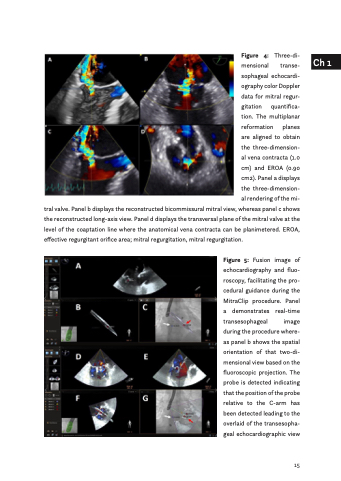

Figure 4: Three-di- mensional transe- sophageal echocardi- ography color Doppler data for mitral regur- gitation quantifica- tion. The multiplanar reformation planes are aligned to obtain the three-dimension- al vena contracta (1.0 cm) and EROA (0.90 cm2). Panel a displays the three-dimension- al rendering of the mi-

tral valve. Panel b displays the reconstructed bicommissural mitral view, whereas panel c shows the reconstructed long-axis view. Panel d displays the transversal plane of the mitral valve at the level of the coaptation line where the anatomical vena contracta can be planimetered. EROA, effective regurgitant orifice area; mitral regurgitation, mitral regurgitation.

Figure 5: Fusion image of echocardiography and fluo- roscopy, facilitating the pro- cedural guidance during the MitraClip procedure. Panel a demonstrates real-time transesophageal image during the procedure where- as panel b shows the spatial orientation of that two-di- mensional view based on the fluoroscopic projection. The probe is detected indicating that the position of the probe relative to the C-arm has been detected leading to the overlaid of the transesopha- geal echocardiographic view